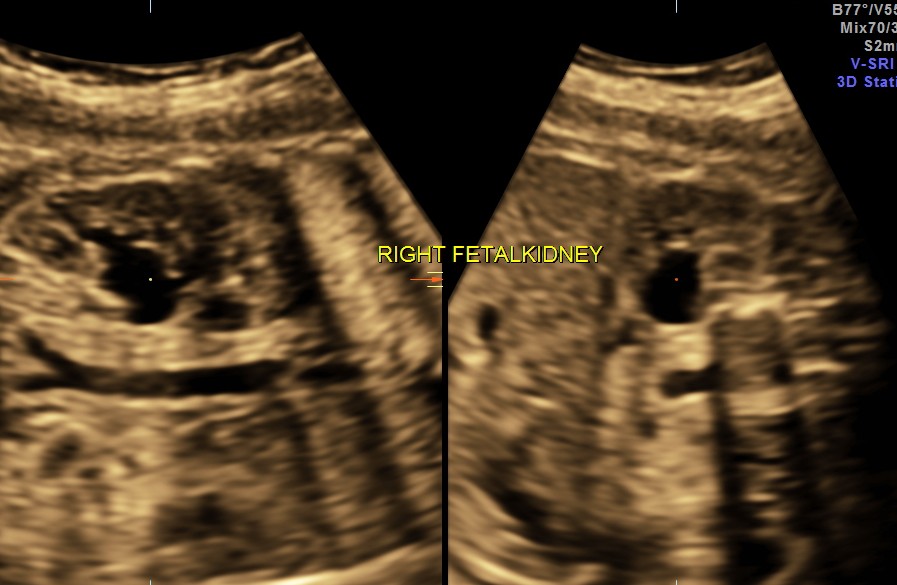

Scan was done at 32 weeks of gestation. Earlier scans have been reported as normal.

The following images show bilateral renal pelvi ectasis and bilateral dilated ureters with all the changes more in the left kidney .